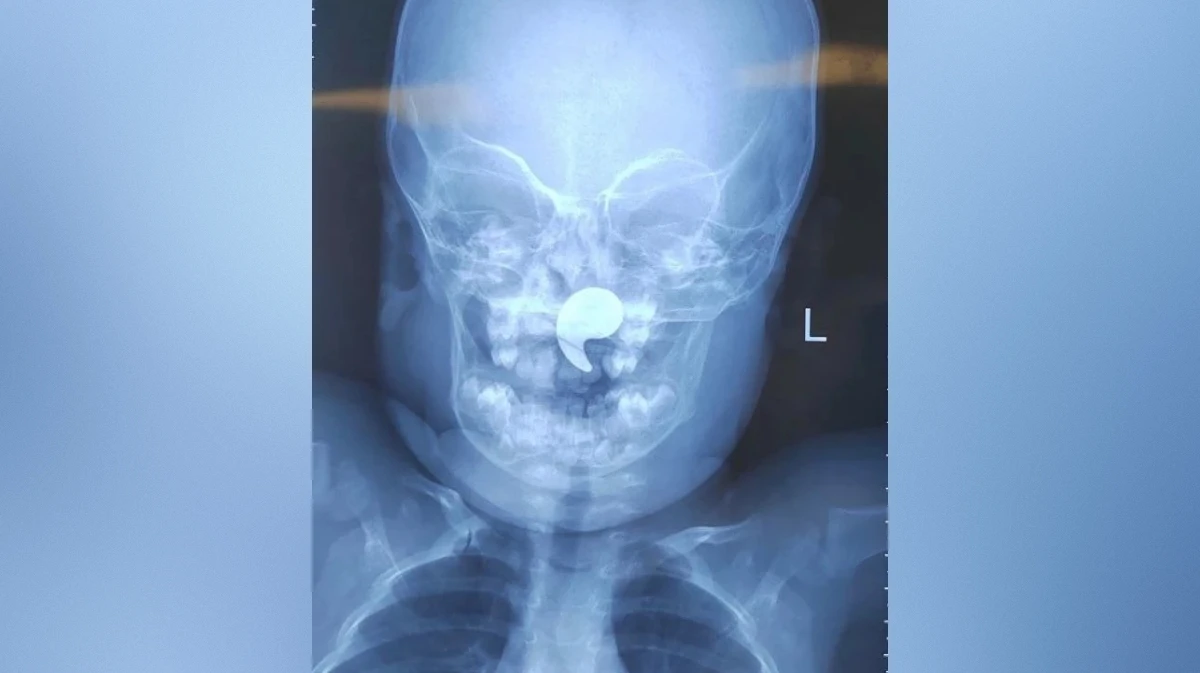

Выяснилось, что девочка играла магнитом в форме запятой. Мать ребенка заметила, что малышка начала давиться, и попыталась извлечь инородное тело пальцем. Так магнит сместился в носоглотку.

Дежурный врач ЛОР-отделения Марина Перепечена под общей анестезией достала магнит под эндоскопическим контролем. Через сутки девочку выписали домой под наблюдение педиатра.